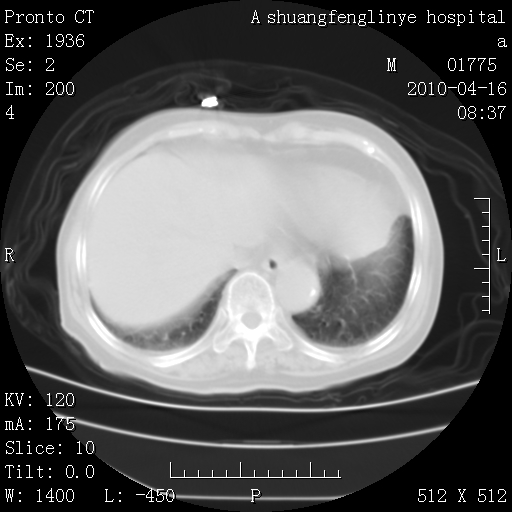

标题: CT25784:咳痰、请会诊!结核? [打印本页]

标题: CT25784:咳痰、请会诊!结核?

考虑左肺上叶增殖灶、纤维灶。

慢支肺气肿,左上陈旧性结核,主动脉冠脉钙化

典型 夹层动脉瘤。 内膜瓣钙化移位

1)左肺上叶结核(纤维、增殖病灶)。2)冠状动脉及主动脉钙化。

1)左肺上叶结核(纤维、增殖病灶)。2)冠状动脉及主动脉钙化。肺动脉高压